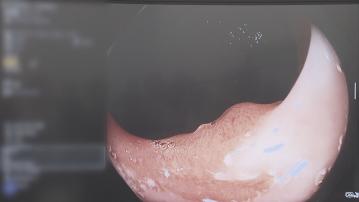

【Now新聞台】中大醫學院成為全球首個在胃鏡檢查加入人工智能輔助的測試基地,團隊指技術能有效快速偵察病變位置及範圍,提升胃癌檢測準確性。

用綠色提示框「狙擊」,就算有多隱蔽病變組織都無所遁形。

中大醫學院早在2021年引入人工智能系統輔助大腸鏡檢查,證實提升腺瘤檢測率高達四成。今年再與日本創科公司合作,應用在胃鏡系統,成為全球首個測試基地。院方表示,系統可以實時鎖定病變位置及範圍,提升早期腫瘤檢測率。

胃部結構有不少皺摺,這套人工智能系統可以快速識別所有可疑病變位置,醫生表示病人做胃鏡的時間可能長了,但就可以確保不會看漏眼。